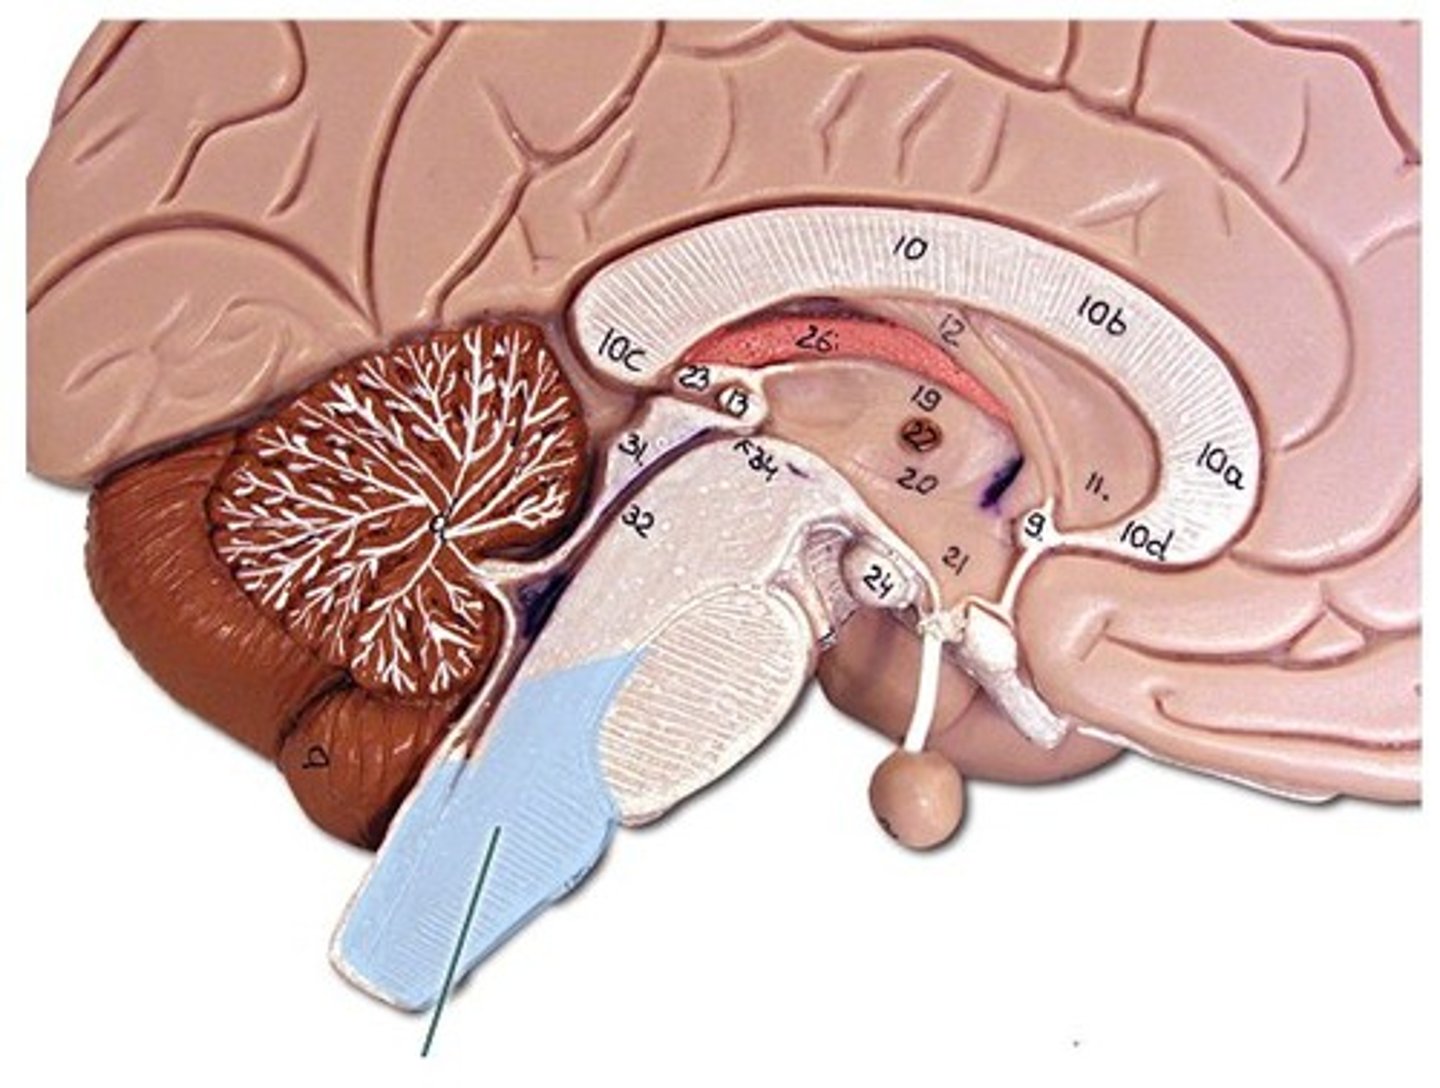

ventricles of the brain

canals in the brain that contain cerebrospinal fluid

lateral ventricles

Ventricles located in each cerebral hemisphere

third ventricle

the ventricle located in the center of the diencephalon

fourth ventricle

between pons and cerebellum

interventricular foramen

opening that connects the lateral ventricles and 3rd ventricle

cerebral aqueduct

connects the third and fourth ventricles

cerebral spinal fluid

made by choroid plexus

CSF function

buoyancy (supports 95% of the weight of the brain), protection (liquid cushion for brain tissue), chemical stability (transports nutrients to brain and waste away from brain)

Hydrocephalus

accumulation of CSF in the spaces of the brain